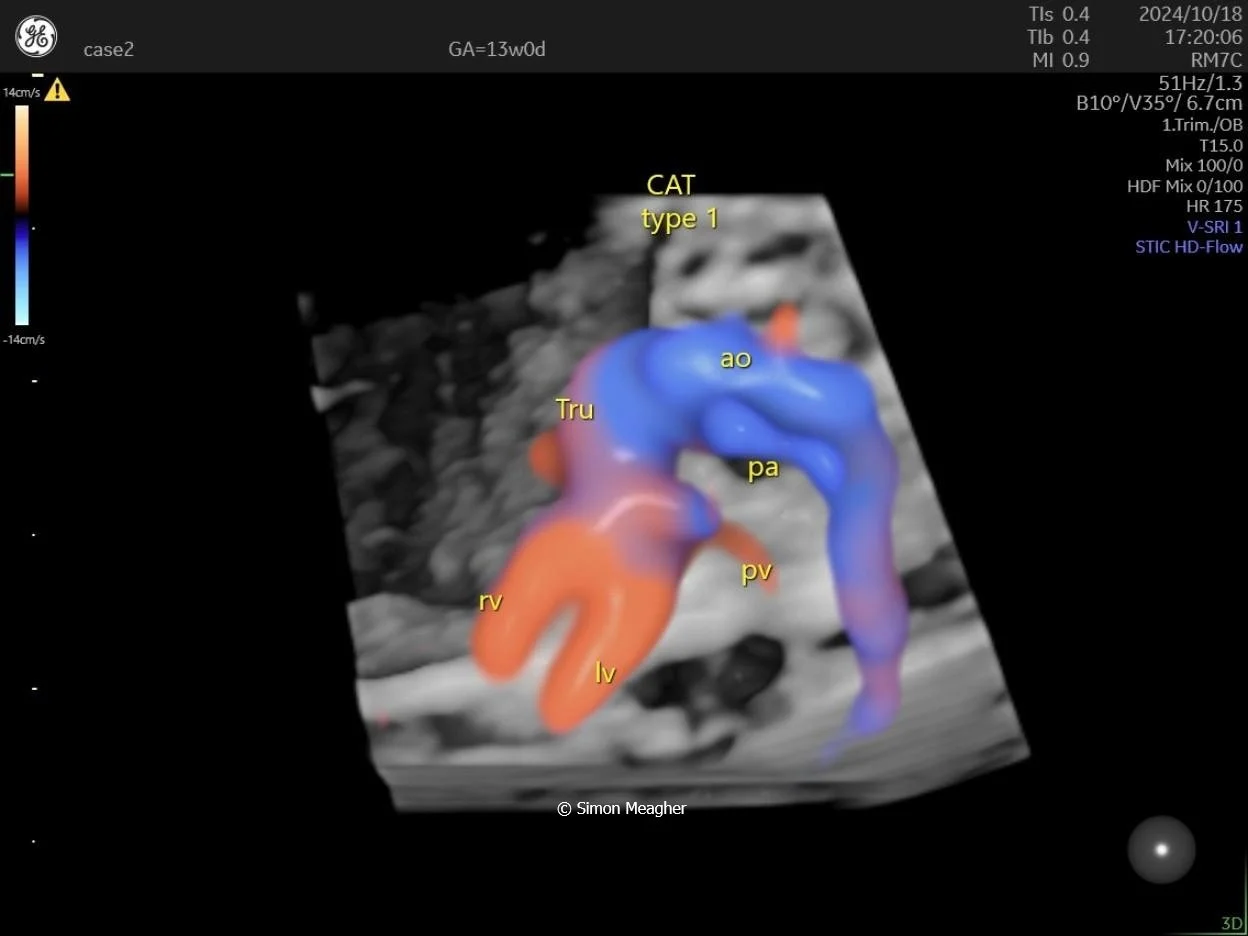

Join Professor Simon Meagher and leading experts for an intensive masterclass designed to transform your clinical practice.

This high-impact, one-day event delivers live scanning demonstrations, real-world case studies, and cutting-edge techniques across all trimesters.